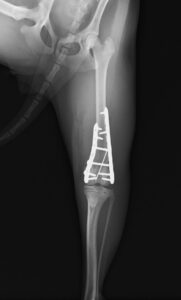

大腿骨の膝に近い部分が骨折してしまっており、さらに単純な骨折ではなかったため、内側と外側にそれぞれプレートを設置し固定しました。

関節に近い場所の手術であったためどうしても術後は関節がある程度拘縮(曲げ伸ばししづらくなる)してしまいますが、徐々に足を着けるようになってくれ、リハビリの効果もあり今では元通り運動できるように回復してくれました。

大腿骨遠位の骨折は特に若齢の犬猫においてしばしば発生します。若齢時には多くの骨の両端に成長板という骨を作る場所があり、その場所は強い力がかかった際に骨折しやすいためです。単純な骨折の場合にはピンだけで整復が可能なことも多くありますが、今回のような状況ではプレート固定も適応になります。どちらにしても手術後に関節の拘縮が起きやすく、術後のリハビリも重要になってきます。当院ではリハビリに特化したスタッフも在籍し、術後のケアもご家族と共に実施していきますので安心して手術を受けて頂くことができます。